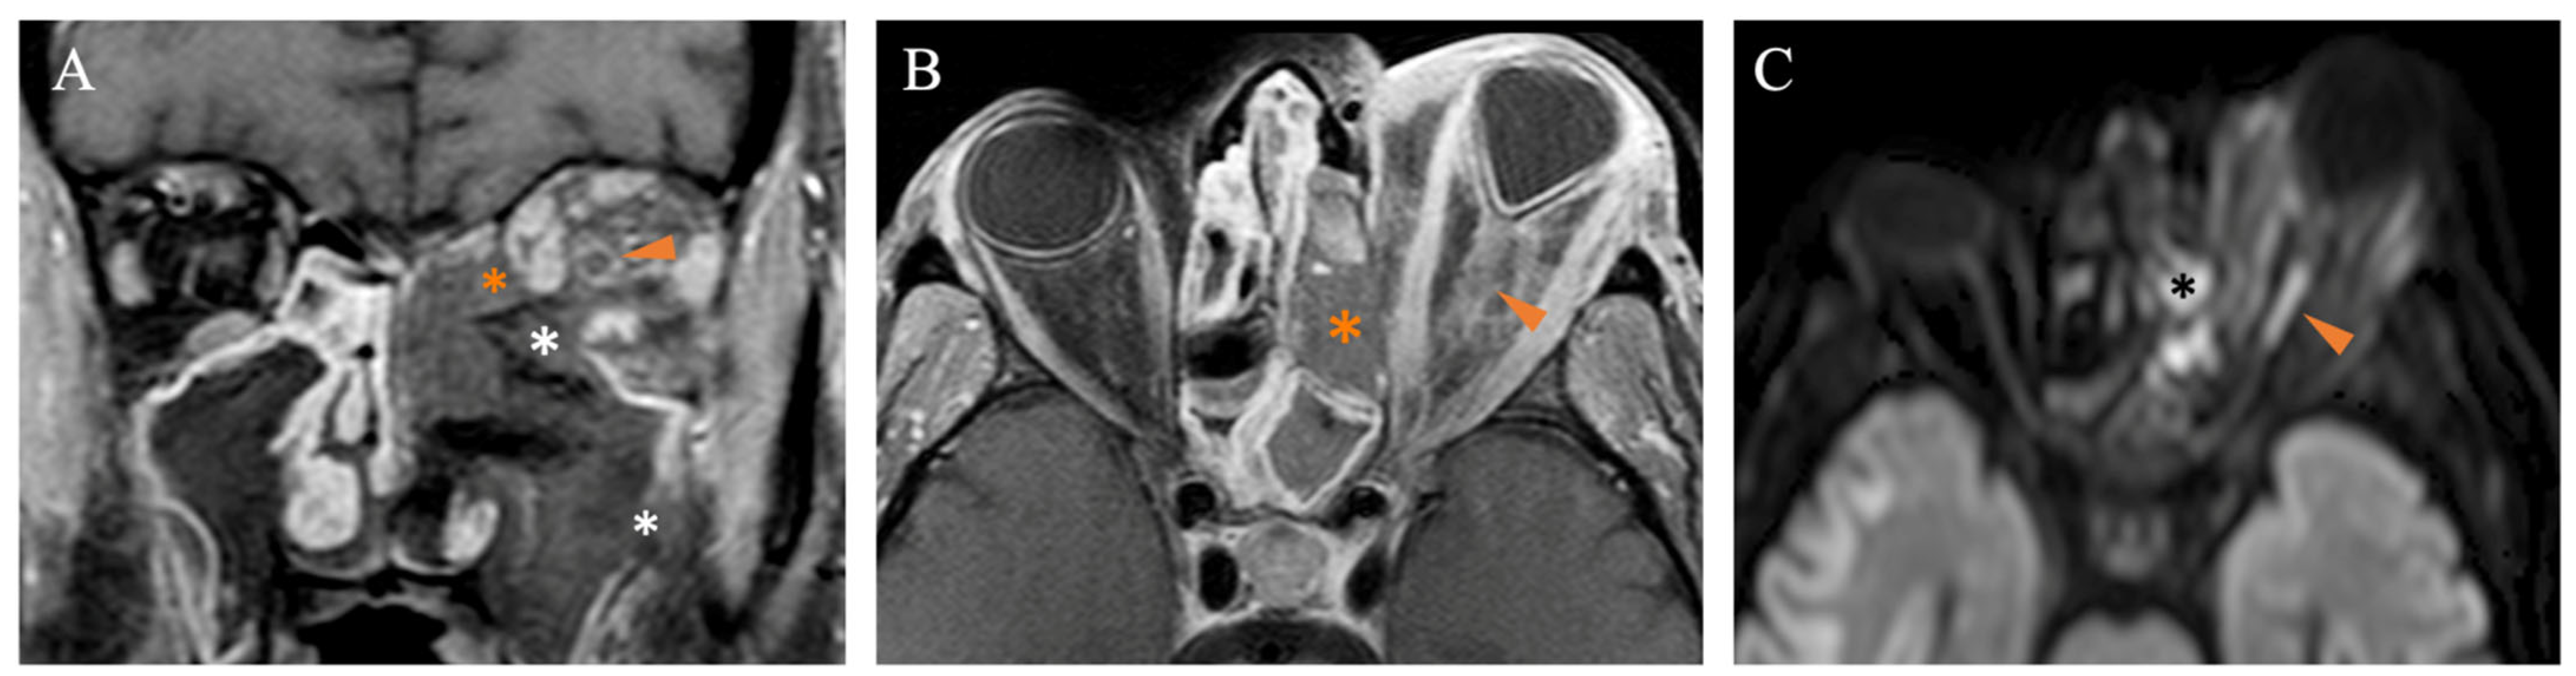

- Kim, J.H.; Kang, B.C.; Lee, J.H.; Jang, Y.J.; Lee, B.J.; Chung, Y.S. The prognostic value of gadolinium-enhanced magnetic resonance imaging in acute invasive fungal rhinosinusitis. J. Infect. 2015, 70, 88–95. [Google Scholar] [CrossRef]

- Dixit, R.; Gupta, A.; Prakash, A.; Pradhan, G.S. Magnetic resonance imaging of rhino-orbito-cerebral mucormycosis: A pictorial review. Acta Radiol. 2023, 64, 1641–1649. [Google Scholar] [CrossRef]

- Becker, M.; Masterson, K.; Delavelle, J.; Viallon, M.; Vargas, M.I.; Becker, C.D. Imaging of the optic nerve. Eur. J. Radiol. 2010, 74, 299–313. [Google Scholar] [CrossRef]